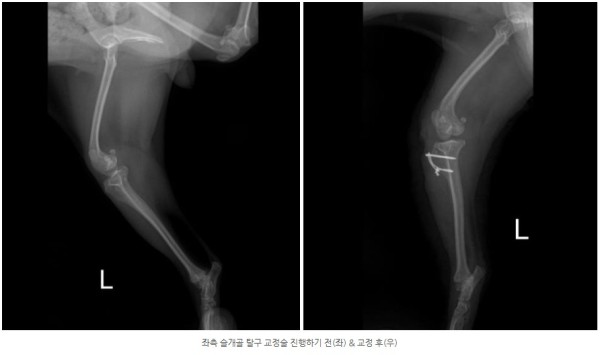

양쪽 모두 안쪽으로 슬개골이 빠지는 내측탈구 4기 상태가 확인되었고

통증의 근본 원인을 해결하기 위해 양측 모두 슬개골 탈구 교정술(MPL)을 진행하기로 결정하였습니다.

교정술 후 5일간 입원하여 24시간 케어를 받고 양호한 컨디션으로 퇴원한 아이는